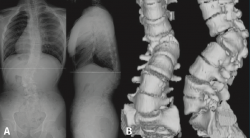

Otros hallazgos radiológicos frecuentes, como las anomalías congénitas de transición lumbosacra, espondilolistesis, secuelas de epifisitis, la espina bífida oculta, las escoliosis leves o moderadas, la hiperlordosis, espondiloartropatía, etc., se encuentran casi por igual en pacientes con y sin dolor lumbar (Figuras 5, 6 y 7)(22,23).

Constituye una técnica muy útil para evaluar las anomalías anatómicas de la columna vertebral (Figura 10).

La TAC visualiza con bastante precisión el tejido óseo, siendo claramente superior a la RM para ello. También permite visualizar los tejidos blandos intra- y paraespinales, aunque la RM es muy superior en la evaluación de estos tejidos, por lo que está siendo desplazada por esta para el estudio de los problemas discales, degenerativos y radiculomedulares (Figura 11).

Entre las principales indicaciones de la TAC, se incluirían la sospecha clínica de hernia discal (Figura 12)(26), la estenosis del canal vertebral lumbar, la fractura vertebral lumbar, los tumores vertebrales, la valoración posquirúrgica tras una cirugía de artrodesis vertebral lumbar y la sospecha de una sacroileitis en el contexto clínico de una posible espondiloartropatía inflamatoria. También es muy útil como herramienta auxiliar en determinados procesos diagnósticos, como por ejemplo en la biopsia de una zona sospechosa y en el diagnóstico postoperatorio de la correcta colocación de implantes en la columna vertebral.